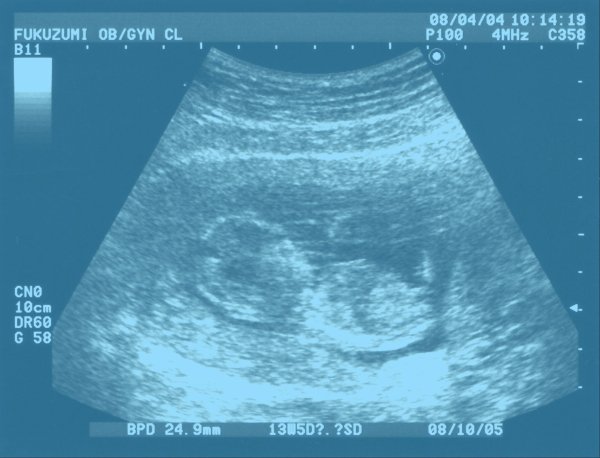

At present, if one of those individuals or couples wants to conceive, they have a few options. A person can buy sperm or eggs, depending on what they need; they can also do as Emma Gibson’s parents did and buy fertilized embryos, which are often donated by parents who have undergone in vitro fertilization (IVF) and do not require the extra gametes created in the process. These sex cells can then be implanted into the uterus via IVF, alongside a cocktail of hormones to prepare the body for pregnancy. A couple can also pay for a surrogate to carry the baby, or adopt a child. A handful of individuals have even undergone experimental procedures to bear a child via a uterus transplant, donated and implanted much like a kidney or liver might be.